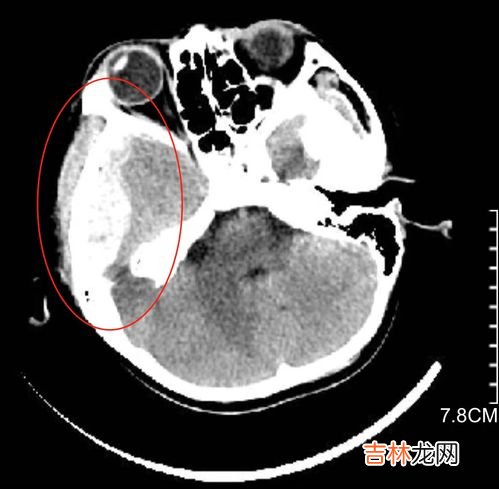

太阳穴遭暴力打击 , 不仅可以因颅骨颞鳞部骨折损伤脑膜中动脉,而且常常可以在颅骨完整的情况下损伤脑膜中动、静脉,在中颅窝基底部形成硬膜外血肿 。脑膜中动脉破裂形成血肿 , 不仅十分迅速,而且后果极为严重 。

脑膜中动脉破裂,可使人立即陷入昏迷,昏迷后的间歇清醒期极短,多则不足1小时 , 少则只有10分钟 , 常常在损伤两小时后完全昏迷 。如果伤后6小时仍不能有效地制止出血,即可以致命 。